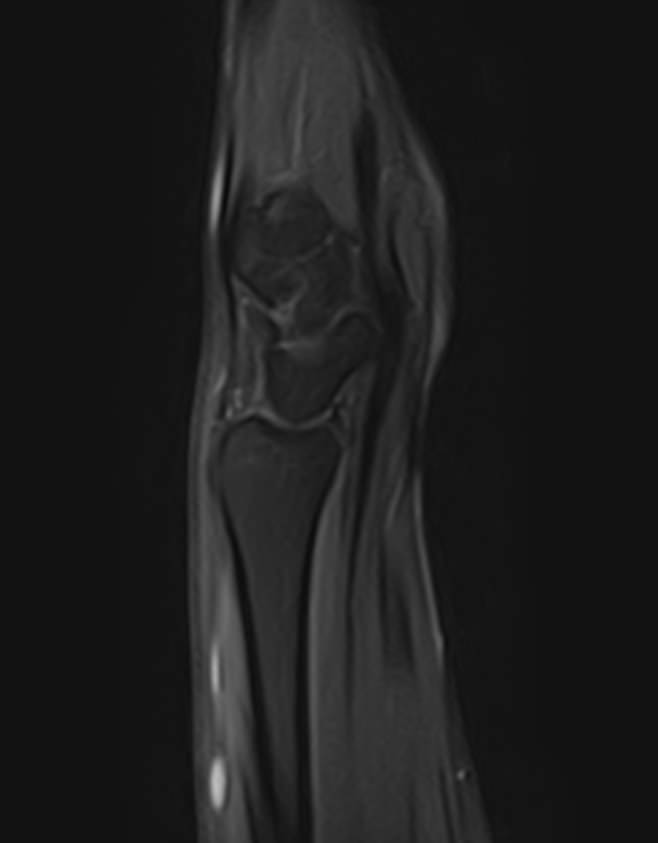

МРТ является современным высокоинформативным неинвазивным и при этом безопасным методом исследования, который позволяет детально визуализировать состояние всех структур лучезапястного сустава, включая дистальные отделы лучевой и локтевой костей, хрящей, сухожилий, нервов и окружающих мягких тканей.

В клинике «Доступная медицина» исследование проводится на новейшем высокопольном томографе экспертного класса TOSHIBA VANTAGE TITAN 1,5 Тесла, который делает послойное сканирование исследуемой области в различных плоскостях с шагом от 1 мм и в дальнейшем преобразует полученные данные в трехмерные изображения. Результаты МРТ позволяют выявлять заболевания лучезапястного сустава на начальных стадиях и назначать своевременное лечение.